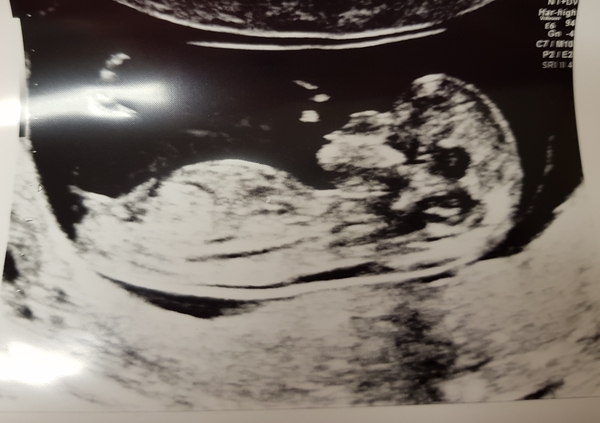

@athers666 what an amazing picture and congratulations @cakelaur yours is amazing too!! Can't believe everyone is getting to/past 12 weeks!! One week tomorrow for me ❤❤

@cakelaur wowsers, loving the pictures! Well happy for you!

Lovely pics @Cakelaur ( your dog 😍) and @Athers666!!! Woohoo second trimester. Less than a week to go to mine now!!

@Athers666 and @Cakelaur amazing amazing photos!! So happy for you both!

Congratulations @Athers666 and @Cakelaur!

I am equally shocked that my little one is 12 weeks 5 days and all healthy!

@Wiggle4 Aww yay, another scan on the thread today! Congrats xx

@Athers666 just gorgeous pic!! So happy for you!

@Wiggle4 you too babe. Lovely clear scan.

Aww Wiggle4! They all look like proper little babies!

@Cakelaur omg those pictures 😍 massive congrats to you hun!! & to everyone else with scans recently that went well, it’s amazing 😊

@Wiggle4 your Scan is so clear. What a perfect little baby. I can’t believe some of us have made it to second trimester already. It’s amazing. Feeling very emotional right now x x x